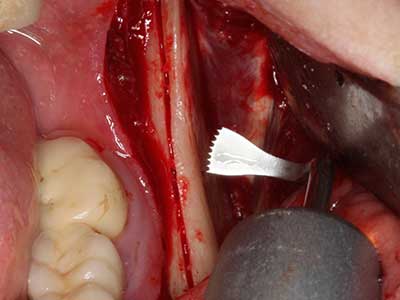

Fig. 18: Preparation of a cortical cover with the piezo bone saw (Piezomed, W&H).

Fig. 19: Surgical site after neurolysis and removal of osteoma.

Fig. 20: The removed bone cover is re-adapted and fixed with an osteosynthesis screw (KLS Martin, Tuttlingen).